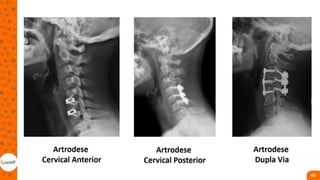

Fraturas da coluna cervical alta

• Cervical alta (c1-c2):

• Lesoes graves;

• Centro respiratório;

• Canal medular com mais espaço

Cervical Baixa (c3-t1)

• responsável por 83% da flexo-

extensão, 90% da inclinação

lateral e por cerca de 50% da

rotação da cabeça;

• As fraturas do tipo compressão

envolvem somente o corpo

vertebral, podendo ser tratadas

de forma conservadora, com

colar Philadelphia, halogesso ou

halovest na maioria dos casos.

• fraturas do tipo explosão podem

ser mais instáveis e, em geral,

são tratadas cirurgicamente por

via anterior;

• As fraturas do tipo distração

envolvem uma lesão anterior

associada a lesões posteriores,

sendo cirúrgicas na maioria dos

casos, necessitando de fixação

por dupla via (anterior e

posterior)